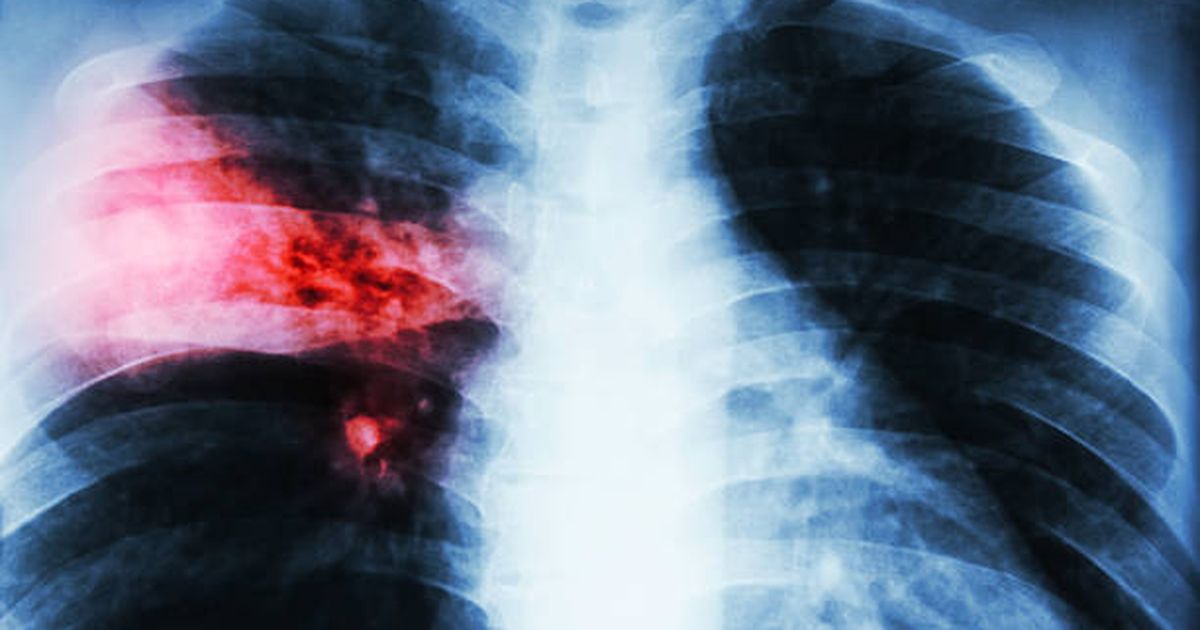

La letalidad por tuberculosis cayó a 8,5% en 2025, el registro más bajo en 23 años

El MSP informó además una reducción de 25% en los fallecimientos, aunque advirtió que los casos y muertes siguen en niveles altos para una enfermedad prevenible y curable.